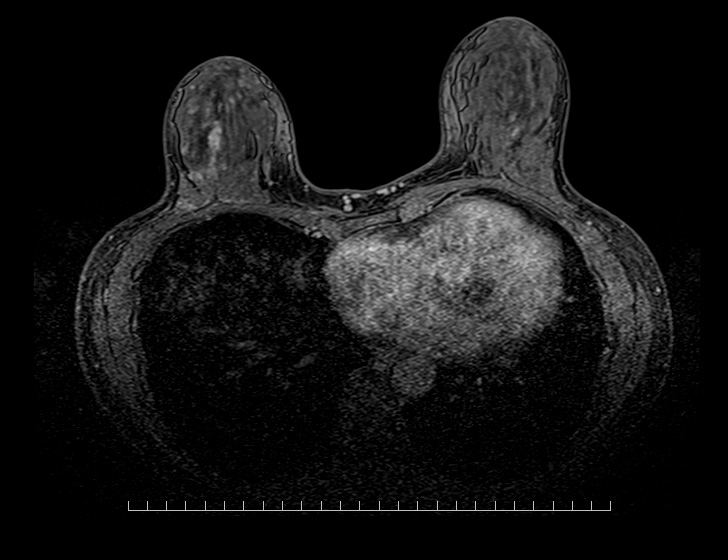

| 撮影可能な部位 | 頭部、脊椎、乳腺、腹部、骨盤部、関節など 全身領域 |

MRI検査依頼書(PDF)当院で撮影したMRI画像